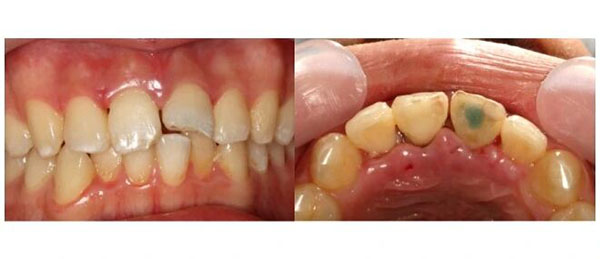

术后1年,复查,牙齿稳稳的。

术后2年,再来,还是好好的。

他已经大学毕业,参加了工作。复查的结果依然是:牙齿稳固,牙周健康。

这8年,那颗曾经差点被拔掉的牙齿,和他一起度过了整个青春,从来没有成为他的困扰。他照常吃饭,照常笑,照常参加面试,照常走进人生的每一个新阶段。